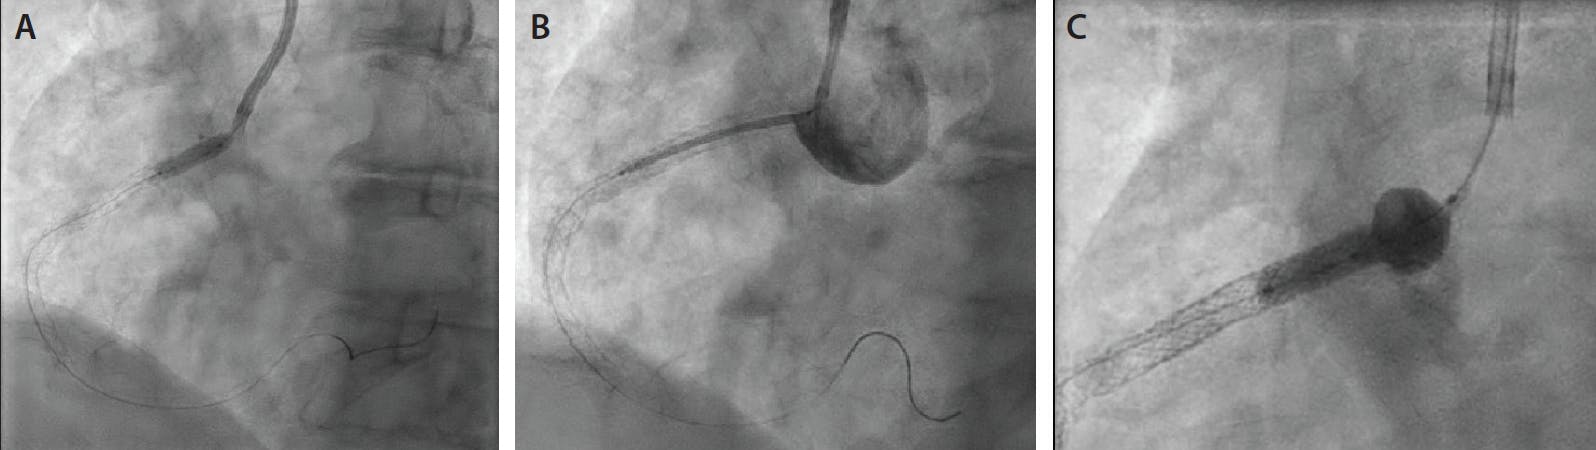

A woman in her early 80s, with a history of hypertension, hyperlipidemia, myocardial infarction, and RCA PCI 15 years earlier, presented to the emergency department with 24 hours of worsening dyspnea and 3 hours of acute-onset chest pain. The initial electrocardiogram showed sub-millimeter ST elevations in the inferior leads, and the initial high-sensitivity troponin was abnormal at 845 ng/L. The patient was referred for emergent coronary angiography and possible PCI. Diagnostic coronary angiography performed through right radial access demonstrated the presence of a culprit ostial RCA stenosis, which was severely calcified with reduced flow. The culprit ostial RCA stenosis was in a de novo, unstented segment of the artery. The nonostial proximal to mid-RCA stents also had substantial nonculprit in-stent restenosis (Figure 1). The left coronary system had no major obstructive disease. The clinical decision was to move forward with culprit ostial RCA PCI of the de novo unstented segment, with the additional plan to treat the mid-vessel in-stent restenosis.

Figure 1. Diagnostic angiography. Orthogonal angiogram views demonstrated the culprit ostial RCA stenosis, which was severely calcified with reduced flow. The culprit ostial RCA stenosis was in a de novo segment of the artery that had not been previously stented (black arrow). The proximal to mid-RCA stents also had substantial nonculprit in-stent restenosis (blue arrow).